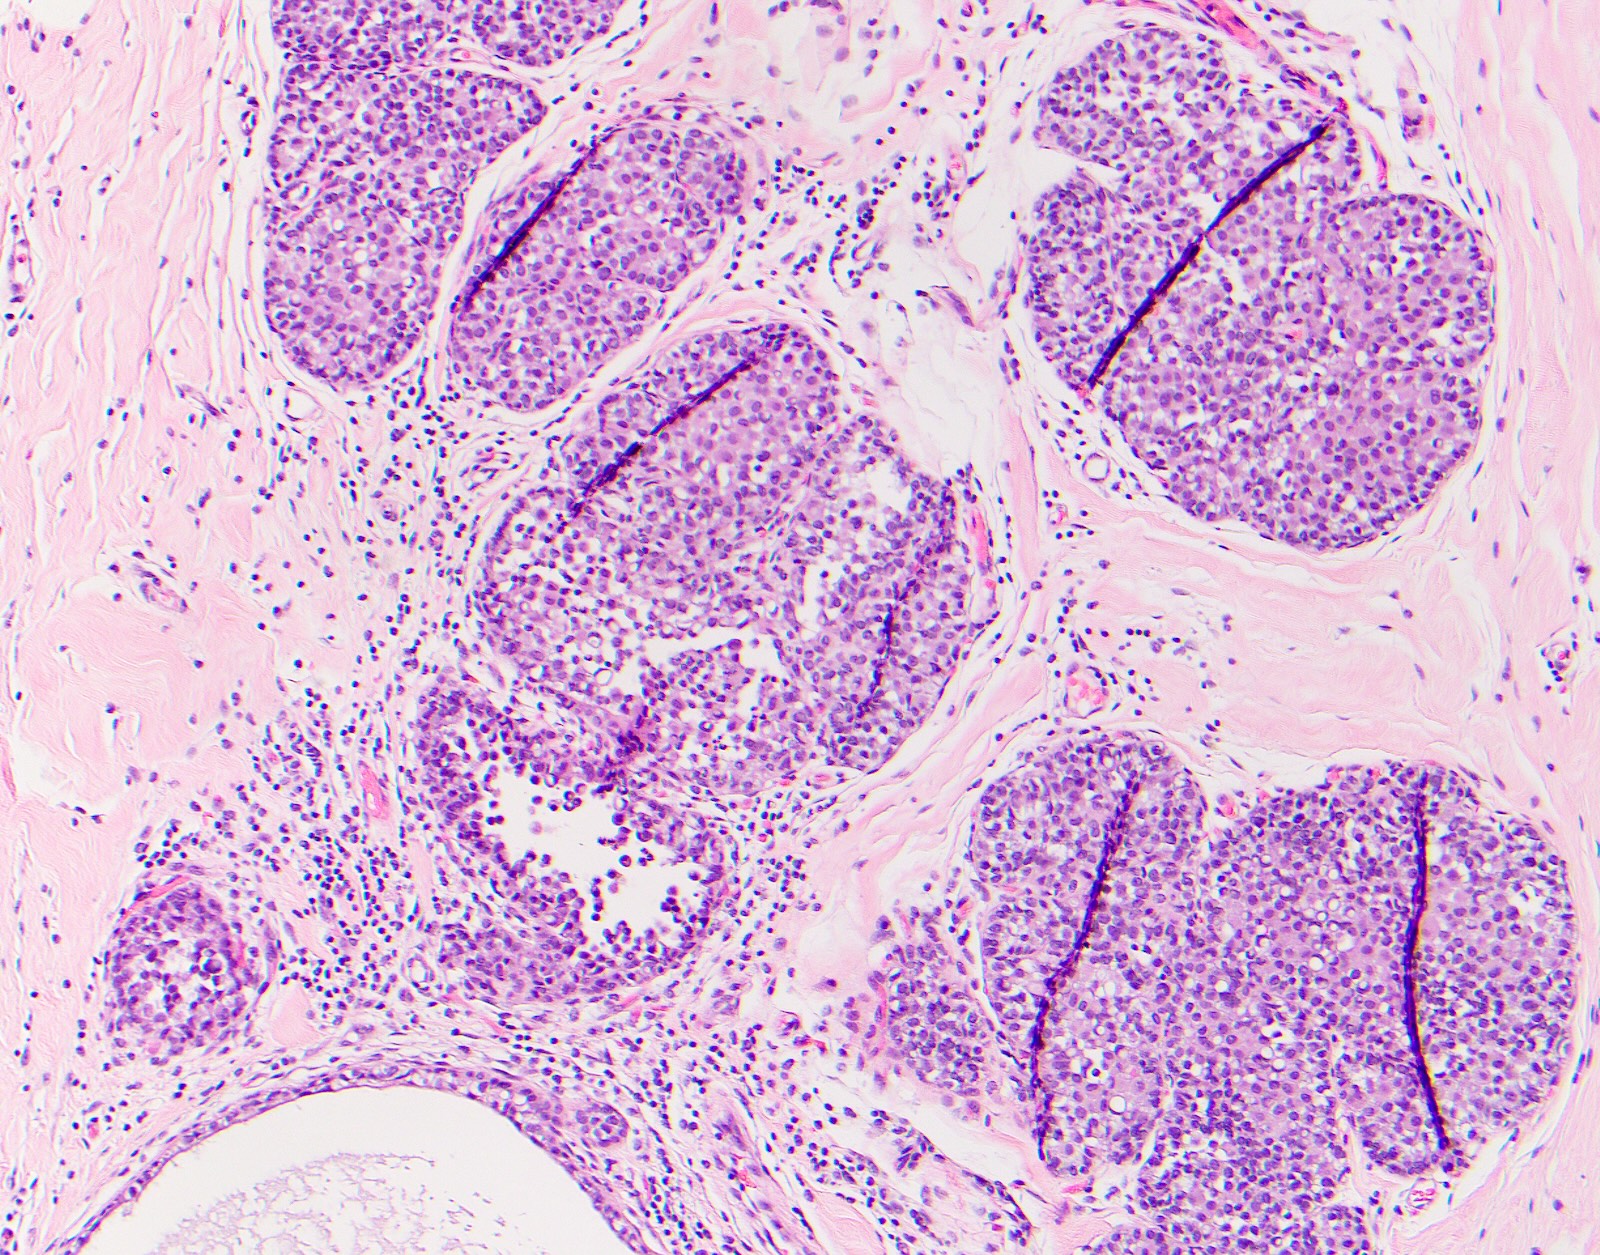

Microscopic (histologic) images

Contributed by Surekha Bantumilli, M.D. and Dimitri G. Trembath, M.D., Ph.D.

- Prostatic basal cell hyperplasia (Hum Pathol 2003;34:462)

- Identification of the basal cell layer in prostate tissue in the determination of carcinoma

Practice question #1

A 65 year old man presents with elevated prostate specific antigen (PSA) and undergoes a prostate biopsy, stained with high molecular weight cytokeratin (HMWCK) (shown above). What is the most likely interpretation of this staining pattern?

- Benign prostate tissue

- Benign seminal vesicle

- High grade prostatic intraepithelial neoplasia

- Prostatic adenocarcinoma

- Urothelial carcinoma

Practice answer #1

A. Benign prostate tissue. The basal layer of benign prostate glands will stain with high molecular weight cytokeratin. Answer D is incorrect because staining will be lost on prostatic adenocarcinoma. Answer C is incorrect because high molecular weight cytokeratin staining can be present in high grade prostatic intraepithelial neoplasia but is not diagnostic by itself for this entity. Answers B and E are incorrect because the glandular appearance outlined by the high molecular weight cytokeratin staining is not consistent with either seminal vesicle or urothelial carcinoma.